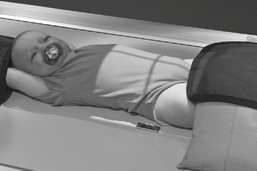

Use only if necessary. Supply with lead apron and gloves, and have parent hold arms above head with one hand and legs with other hand, preventing rotation.

If necessary, have parent hold arms overhead with one hand, and with other hand hold legs to prevent rotation of pelvis or thorax (provide with lead apron and gloves).